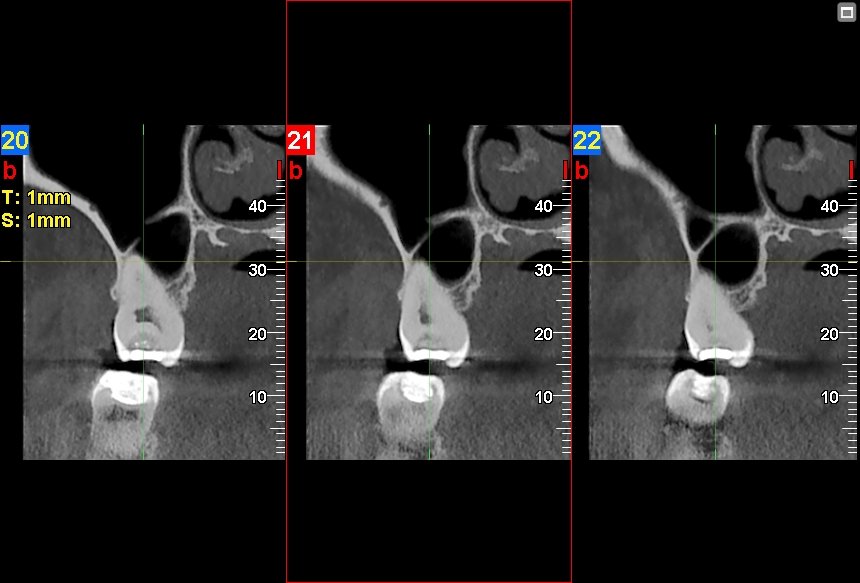

Imágenes 2D-3D Radiografías, Tomografías DENTAL, ATM, SPN, OIDO

Nuestra tecnología Cone Beam 3D permite visualizar estructuras óseas y dentales con alta definición, favoreciendo diagnósticos exactos y resultados clínicos confiables.

"Tenía molestias en la articulación de la mandíbula y me recomendaron hacerme una tomografía de ATM. El proceso fue rápido y profesional. Gracias a los resultados mi tratamiento fue más acertado."

Valeria Mena